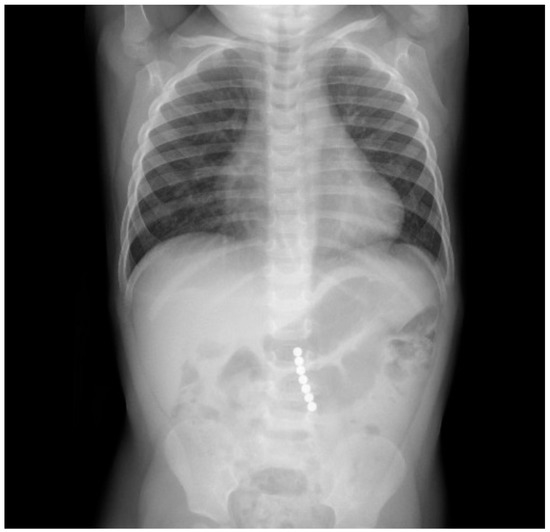

A 2-year-old boy was taken into the emergency department 3 hours after ingestion of 7 magnets of 5 mm diameter, which belonged to a building toy. During ingestion, the boy showed no signs of dyspnoea, coughing, or gaging, and afterward, no problems in swallowing. During the physical examination, the abdomen was soft without tenderness on palpation or signs of organomegaly with regular bowel sounds and unremarkable cardiopulmonary examination. An X-ray revealed 7 contiguous, round, radiopaque foreign bodies in projection to the mid-abdomen at LWK 3–5 level with a total length of 3.8 cm and with an adjacent, low-prominence, gas-filled loop of bowel with a maximum diameter of 3 cm with otherwise nonspecific bowel gas distribution. There was no free gas intra-abdominally. The conventional radiological image (Figure 4) was interpreted as a projection of the magnets onto the small intestine, whereby one distance between the beads appeared larger than the others and gave the impression of pinched tissue, giving the indication for diagnostic laparoscopy and foreign body extraction to avoid the occurrence of small intestine or colon perforation.

Figure 4. Conventional radiography showing the ingested magnets.